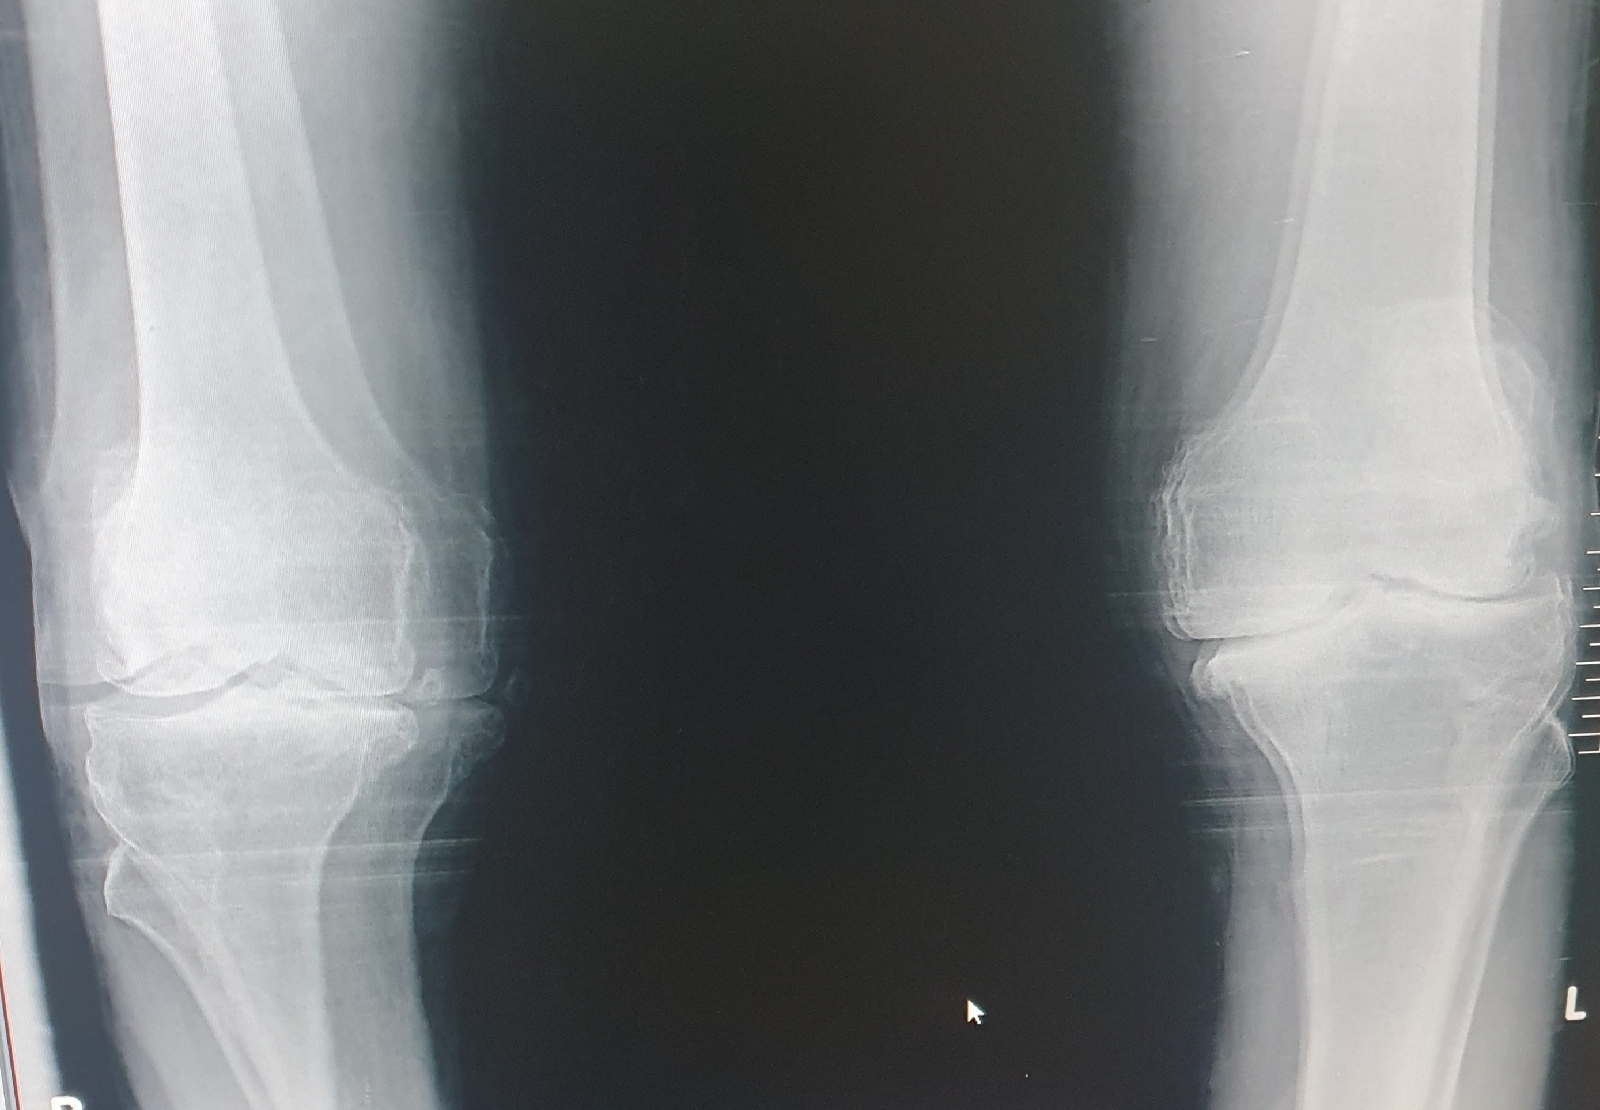

2 years back patient developed bilateral knee pain for which he was diagnosed with osteoarthritis and then he was also diagnosed with hypertension and he was on medication for few days Then he stopped taking medication and neglected.